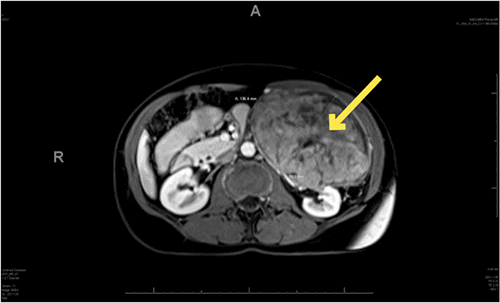

The patient is a 54-year-old woman who presented to the clinic with a one-year history of left-sided abdominal discomfort, fullness, and distension. She noted occasional constipation over the year but denied fevers, night sweats, unexpected weight loss, worsening fatigue, nausea, or vomiting. A palpable mass was appreciated on physical exam. Laboratory values on her complete blood count and comprehensive metabolic panel were unremarkable. Her primary care physician obtained an ultrasound demonstrating a heterogenous retroperitoneal mass measuring 15 cm × 9 cm × 14 cm arising from the left adrenal gland or left kidney. Subsequent magnetic resonance imaging of the abdomen performed at an outside institution (Figure 1) confirmed a 12 cm × 9 cm × 16 cm left-sided retroperitoneal mass displacing the left kidney and the pancreas. Although the mass was well-circumscribed, the origin of the mass was unclear. Intralesional regions of low intensity suggested central necrosis.

Figure 1. T1 Weighted MRI Images of Renal Leiomyoma in Axial. Published with Permission

A) Image depicting without intravenous contrast

B) Image depicting with intravenous contrast

C) Image depicting coronal at its largest dimensions